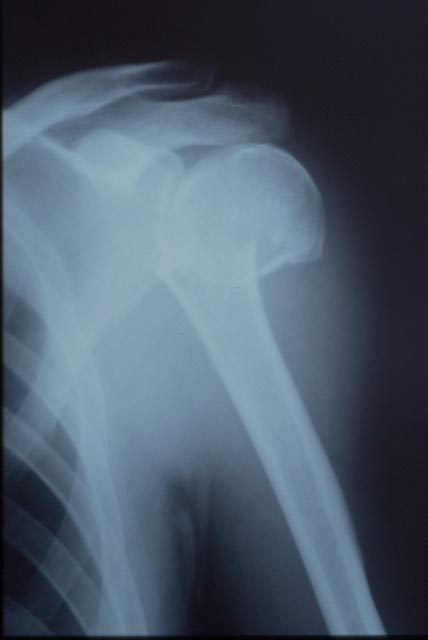

上腕骨近位端骨折

レントゲン検査で確定されます。骨折は

転位のない症例(ずれのない症例)から転位を認める症例(ずれている症例)や結節部での骨折など様々なタイプが存在します。詳細な情報はCTで検討されます。